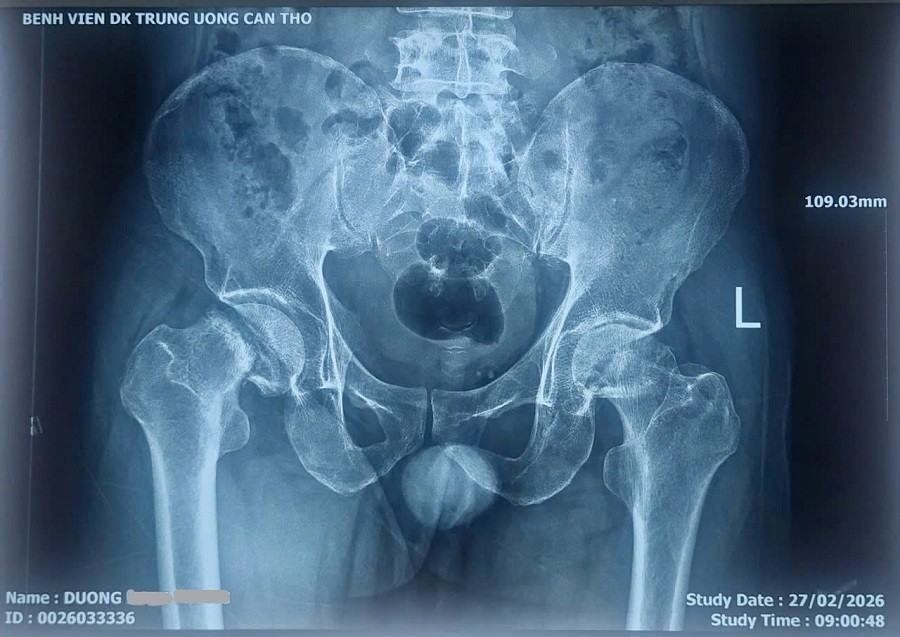

X-Quang khung chậu trước phẫu thuật

Bệnh nhân Dương H. P. (SN 1977) địa chỉ thành phố Cần Thơ, nhập viện tại Bệnh viện Đa khoa Trung ương Cần Thơ ngày 28 tháng 2 năm 2026 trong tình trạng đau khớp háng hai bên kéo dài nhiều năm, đặc biệt tăng nhiều trong khoảng 06 tháng gần đây, phải thường xuyên sử dụng thuốc giảm đau và gặp khó khăn khi đi lại.

Qua thăm khám và các xét nghiệm hình ảnh, các bác sĩ xác định bệnh nhân bị Hoại tử chỏm xương đùi hai bên – một bệnh lý nguy hiểm của khớp háng do giảm hoặc mất nguồn máu nuôi chỏm xương đùi, dẫn đến hoại tử xương, đau kéo dài và có thể gây xẹp khớp nếu không điều trị kịp thời.Bệnh nhân có chỉ định phẫu thuật.